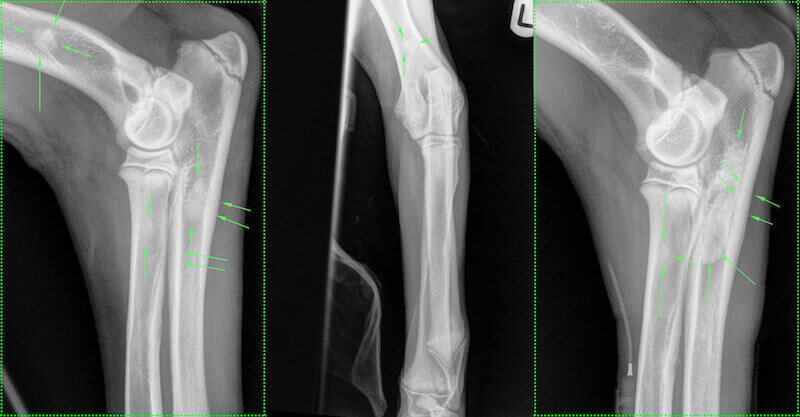

Mediolateral and craniocaudal views of the left elbow and a mediolateral projection of the right elbow are shown.

The lesions seen in these images are as classically described for the middle radiographic phase of panosteitis, however, radiographic changes may be more subtle depending on severity of the condition and the timing of radiographs.

The green arrows highlight the sclerotic radiodensities in the diaphyses of the humerus, radius and ulna (left mediolateral view), humerus (left craniocaudal view) and radius and ulna (right mediolateral view). The arrows also highlight endosteal and periosteal involvement with cortical thickening in both mediolateral views.

Radiographic changes may be subtle early in the course of the disease and may include increased radiolucency in the region of the nutrient foramen followed by blurring and accentuation of trabeculae. If changes are not apparent on initial radiographs further images should be obtained several weeks later.  In the middle phase sclerotic radiodensities appear, particularly at the proximal and distal ends of the diaphysis. Endosteal and/or periosteal involvement may be evident, eventually resulting in a thickened cortex.  Late in the disease, opacities resolve, leaving coarse, thickened trabecular bone that eventually normalises, although cortical thickening may persist. The histological and radiological course of the disease lasts about 90 days in a particular bone.